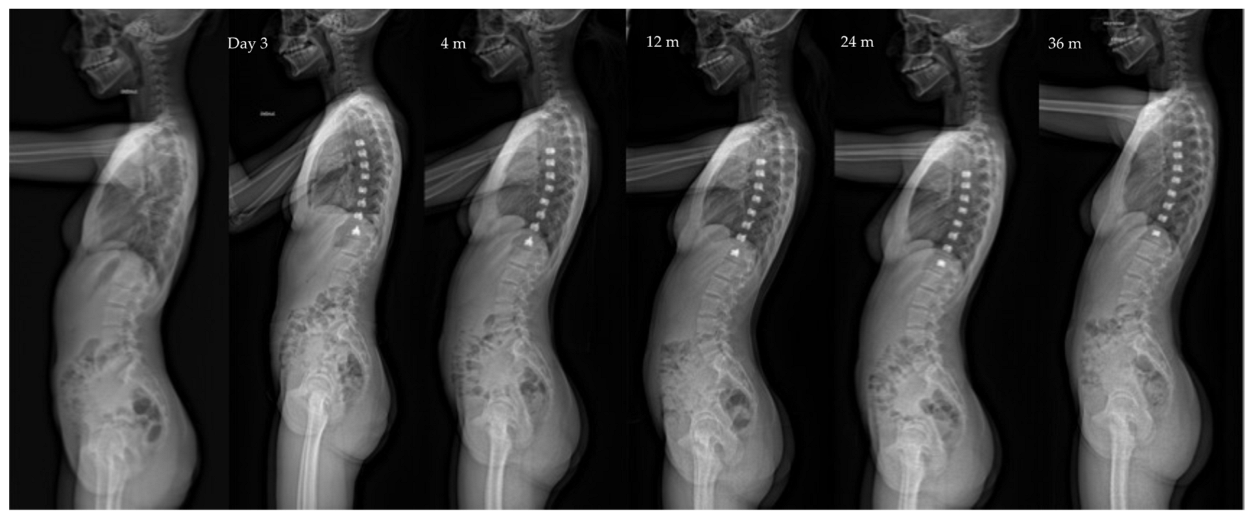

| Major curve | 49°(8,9°) | 27°(12°) | 22°(12°) | 19°(14°) | <0.01 |

| Kyphosis (T1–T12) | 20°(13°) | 23°(13°) | 25°(12°) | 24°(14°) | 0.06 |

| Lordosis (L1–L5) | 36°(12°) | 32°(13°) | 40°(7°) | 40°(8°) | 0.07 |